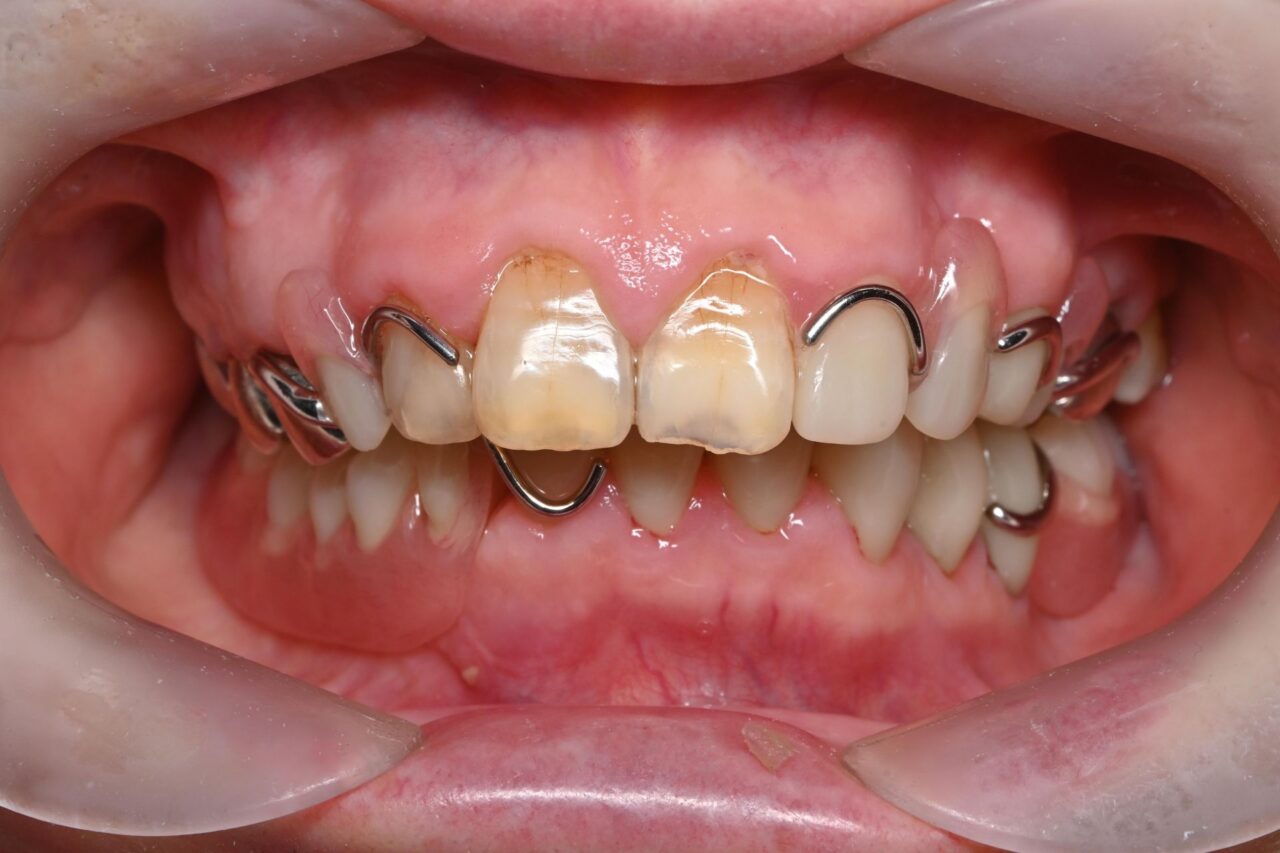

初診時の状態

正面

下の歯が全く見えません。

奥歯が無くなって噛み込みが深くなってしまい、下の前歯が上の歯茎に刺さっている状況です。